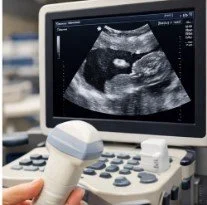

An abdominal ultrasound is a painless imaging test that uses sound waves to capture real-time pictures of your abdominal organs. It is commonly used to diagnose issues related to:

2. A warm gel is applied to the abdomen to help the sound waves travel.

3. A handheld device (transducer) moves across your abdomen to capture images.

4. The radiologist interprets the images and sends a report to your doctor.